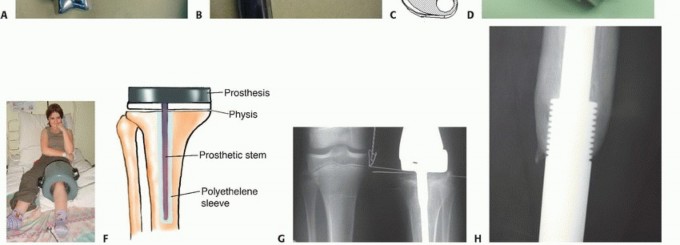

آليات التمدد المختلفة

تطورت آليات تمديد الأطراف الصناعية بشكل كبير على مر السنين:

- الأطراف الميكانيكية القابلة للتمدد (Mechanically Expandable Prostheses):

- كانت هذه هي التقنية الأولية.

- تتطلب جراحة بسيطة كلما احتاج الطرف للتمديد. يقوم الجراح بإجراء شق صغير، ثم يستخدم أداة خاصة لتمديد الطرف الصناعي ميكانيكيًا.

- على الرغم من فعاليتها، إلا أنها تتطلب تخديرًا وجراحة متكررة، مما يزيد من خطر العدوى والمضاعفات.

- الأطراف المغناطيسية القابلة للتمدد (Magnetically Expandable Prostheses):

- تمثل هذه التقنية أحدث الابتكارات وأكثرها شيوعًا حاليًا.

- تحتوي على محرك مغناطيسي صغير مدمج داخل الطرف الصناعي.

- يتم تمديد الطرف خارجيًا باستخدام جهاز تحكم مغناطيسي خاص (External Magnetic Field Controller) يوضع على جلد الطفل فوق الطرف الصناعي.

- لا تتطلب أي تدخل جراحي للتمديد، مما يقلل بشكل كبير من مخاطر العدوى والإزعاج للطفل.

- يمكن إجراء التمديد في العيادة الخارجية بواسطة الأستاذ الدكتور محمد هطيف، مما يجعل العملية سهلة ومريحة.

مكونات الطرف الصناعي القابل للتمدد

يتكون الطرف الصناعي القابل للتمدد عادةً من:

* مكونات معدنية: غالبًا ما تكون مصنوعة من سبائك التيتانيوم أو الكوبالت-كروم، وهي مواد متوافقة حيويًا وقوية.

* مكونات مفصلية: تحاكي وظيفة المفصل الطبيعي (مثل الركبة أو الكتف)، وتكون مصنوعة من البولي إيثيلين عالي الكثافة أو السيراميك.

* آلية التمدد: الجزء المركزي الذي يسمح بتغيير طول الطرف (ميكانيكي أو مغناطيسي).

* أدوات التثبيت: مسامير أو أسمنت عظمي لتثبيت الطرف الصناعي بالعظم المتبقي للطفل.